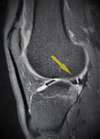

L’IRM (ou l’arthroscanner) confirme l’existence d’une lésion méniscale et sa localisation.